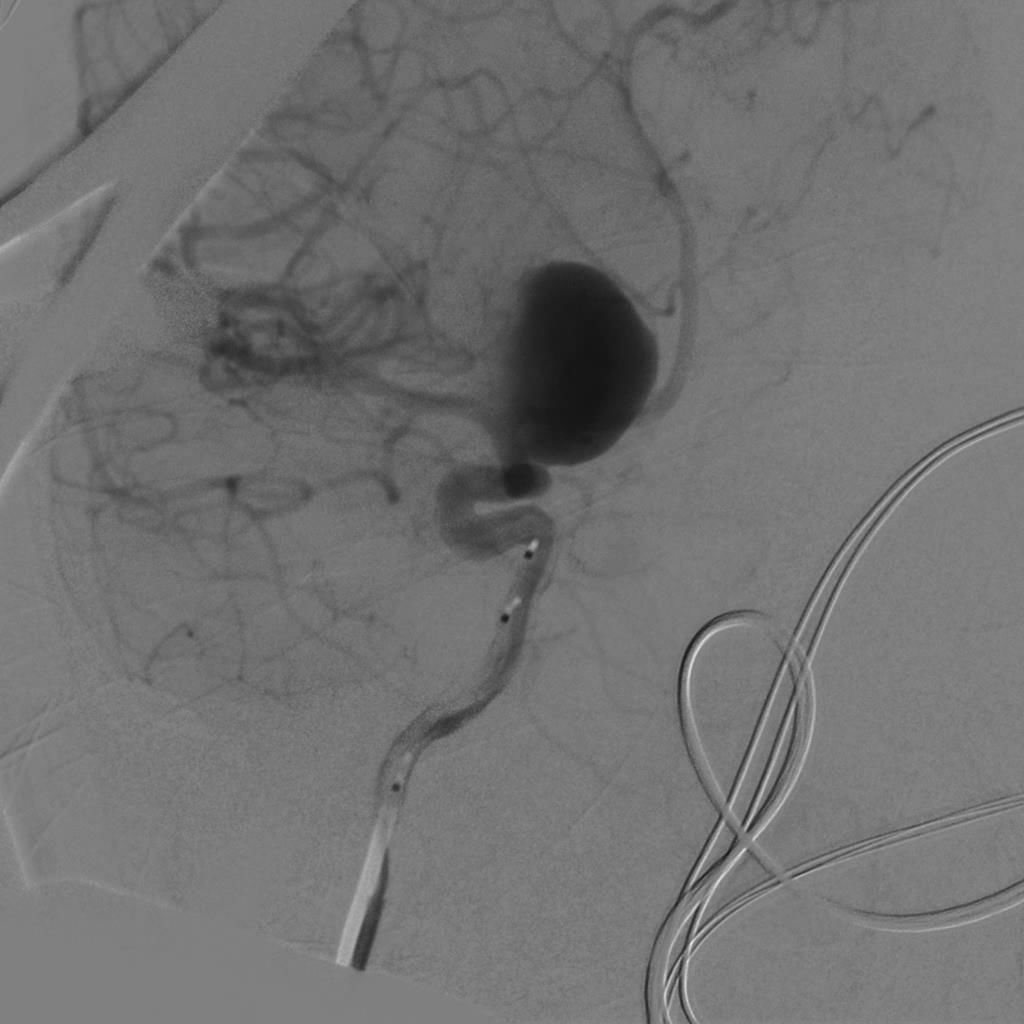

全身肝素化后,路图下将6FGuiding导引导管放置于右侧颈内动脉岩谷水平段,使用Scepter球囊微导管在014微导丝带领下超选进入颈内动脉岩谷垂直段,充盈球囊,造影显示阻断颈内动脉满意后继续手术。

球囊到位

球囊充盈,虚线为球囊

球囊阻断满意,造影剂返流至颈外动脉,虚线为球囊